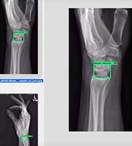

Wrist Bone

Wrist Bone Trauma AI

Machine Learning-Aided Diagnosis Enhances Human Detection of Perilunate Dislocations.

Pridgen B, von Rabenau L, Luan A, Gu AJ, Wang DS, Langlotz C, Chang J, Do B. Automatic Detection of Perilunate and Lunate Dislocations on Wrist Radiographs Using Deep Learning. Plast Reconstr Surg. 2024 Jun 1;153(6):1138e-1141e. doi: 10.1097/PRS.0000000000010928. Epub 2023 Jul 17. PMID: 37467052.

Luan A, von Rabenau L, Serebrakian AT, Crowe CS, Do BH, Eberlin KR, Chang J, Pridgen BC. Machine Learning-Aided Diagnosis Enhances Human Detection of Perilunate Dislocations. Hand (N Y). 2025 Jan 15:15589447241308603. doi: 10.1177/15589447241308603. Epub ahead of print. PMID: 39815415; PMCID: PMC11736725.